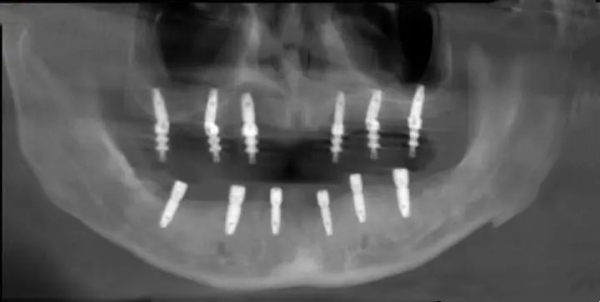

再看診療設(shè)備,家鴻一點(diǎn)都不吝嗇,引進(jìn)了各種高端的口腔設(shè)備,比如芬蘭口腔數(shù)碼全景X光機(jī),還有全套的醫(yī)院感染控制設(shè)備,既能穩(wěn)準(zhǔn)診斷病情,又能可能會(huì)診療過(guò)程的可靠。就拿種植科來(lái)說(shuō),這里有專門人員近十名,掌握高端的微創(chuàng)種植技術(shù),不管是即刻種植、上頜竇提升同期種植,還是數(shù)字化導(dǎo)板種植,都能熟練操作,幫很多牙列缺損的患者重新找回咀嚼功能。